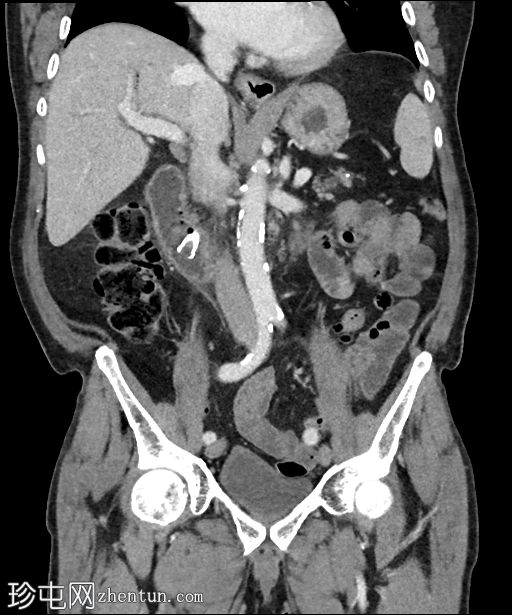

冠状位增强扫描(门静脉期)

可见胆道支架位置良好,管腔内可见分层气液平面。支架远端位于充满液体的D2段内。支架内未见明显放射性结石。

肝内胆管未扩张,但可见胆道积气。

胰头水肿,伴胰周脂肪浸润。未见明显积液。

胰头局灶性结节(代表已知的肿瘤),伴有上游主胰管扩张,位于萎缩的胰颈、胰体和胰尾内。背景可见胰腺实质内钙化。